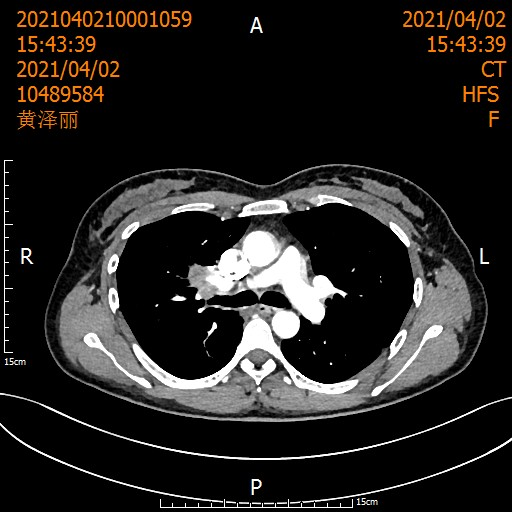

遵循《国际专家共识》,刘浩团队启动了术前2周期化疗联合3周期"卡瑞利珠单抗+紫杉醇/卡铂"治疗。

治疗后患者影像

经过术前新辅助治疗后,医生又为她精心策划了根治性手术,团队紧密配合,顺利完成。